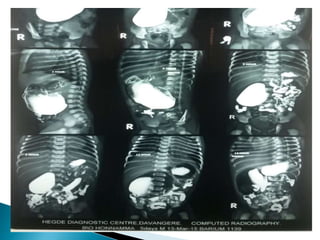

 MCU done on D4 of life s/o bilateral vesicoureteric

reflux,grade3 on RT & grade2 on LT.

photherapy.MCU done on d5 s/o Bilateral

vesicouretral reflux grade 3 on Rt and grade2

on Lt.Started prophylactically sporidex drops